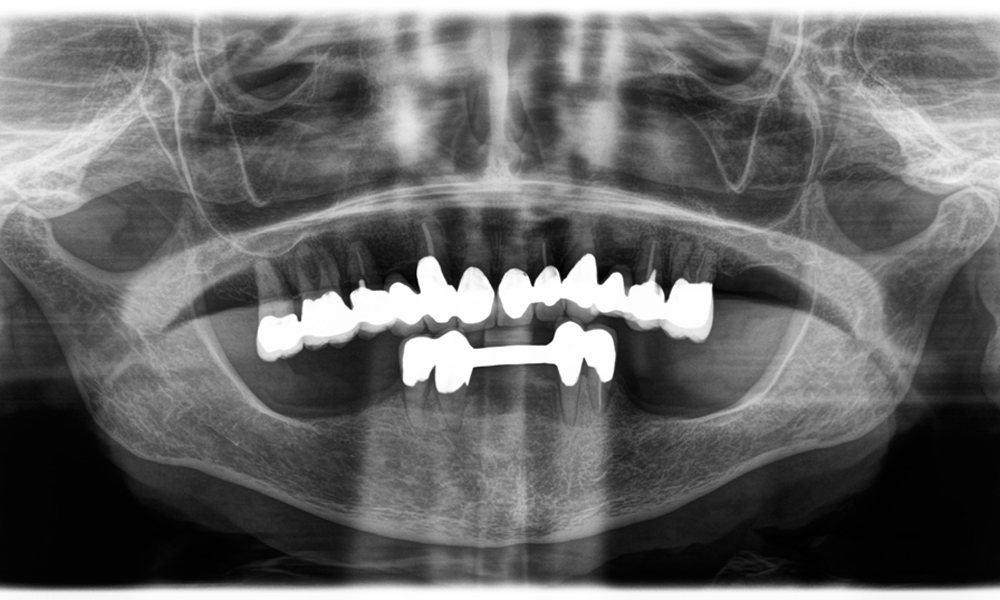

Un deuxième cas illustrant les capacités cliniques du Power Edition concernait le remplacement d'une couronne en zircone endommagée chez une patiente de 63 ans. La patiente présentait une facette ébréchée sur sa couronne en zircone vieille de 20 ans sur la dent 6. Malgré l'emplacement postérieur, la patiente trouvait le défaut gênant et demandait une nouvelle restauration.

Le Power Edition a permis un sectionnement précis, grâce à un couple accru et un refroidissement amélioré qui ont contribué à l'ablation contrôlée de la couronne sans perte importante de matière. Le système de serrage et le couple amélioré se sont avérés essentiels dans ce processus.